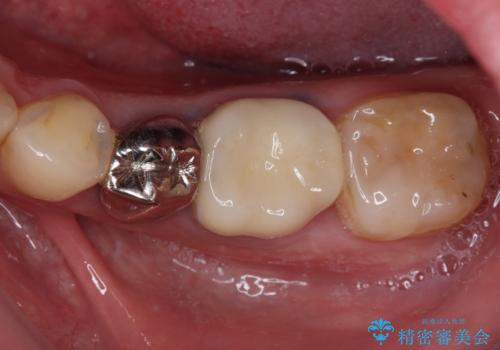

欠損と治療途中の奥歯 インプラント治療と補綴治療

欠損部はインプラントによる補綴治療を、土台の外れてしまった歯は、根管治療を行った上で、補綴治療を行うこととしました。

骨格的に下顎が大きく上顎が小さいため、奥歯に力の負担のかかりやすい咬み合わせであるので、治療後は睡眠時にマウスピースを装着することで、セラミッククラウンやインプラント、治療をしたご自身の歯が長持ちするよう指導しています。